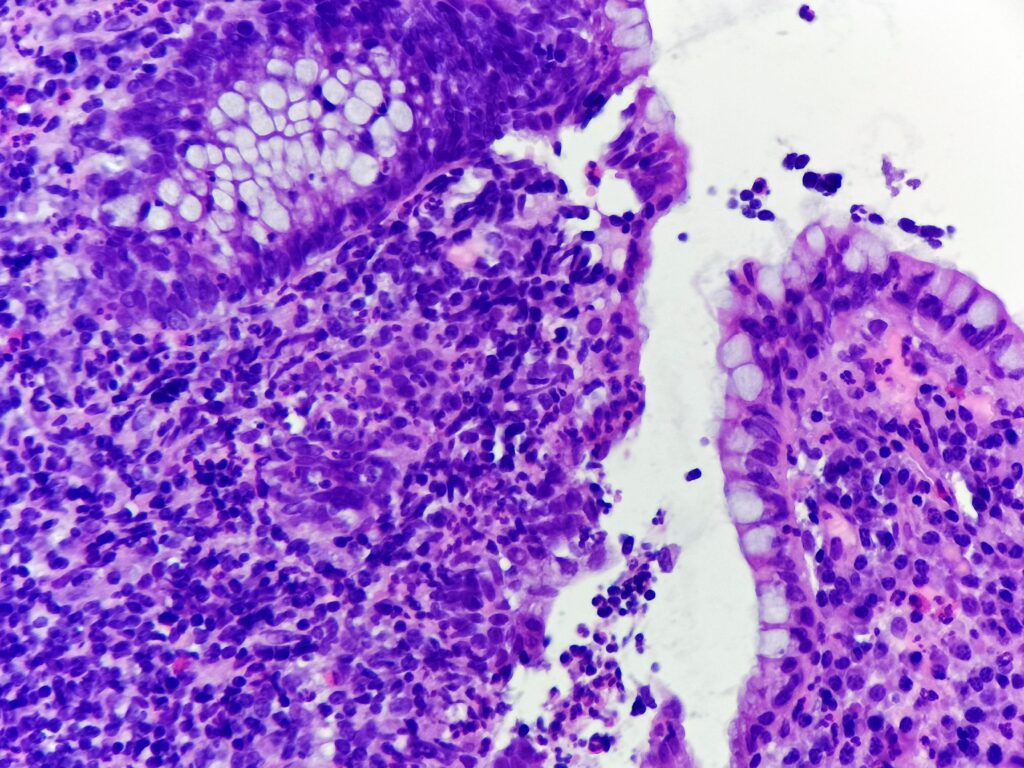

Pacjentka 57 letnia z wieloletnim wywiadem wrzodziejącego zapalenia jelita grubego przyjęta do Poradni Endoskopowej w trakcie klinicznego zaostrzenia objawów. Klinicznie wykluczono odczyny polekowe oraz czynniki infekcyjne. W kolonoskopii w odbytnicy, esicy, zstępnicy i poprzecznicy stwierdzono obrzękniętą, nierówną, wyboistą błonę śluzową z nadżerkami i polipami rzekomymi, krwawiącą kontaktowo. Ze zmienionych obszarów pobrano wycinki.

- zapalenie ograniczone do blaszki właściwej błony śluzowej jelita grubego

- naciek zapalny składający się z limfocytów, plazmocytów (w tym charakterystycznie u podstawy krypt, niebieska strzałka), makrofagów, granulocytów kwasochłonnych i granulocytów obojętnochłonnych

- wnikanie granulocytów obojętnochłonnych do nabłonka powierzchownego i kryptowego, tworzenie ropni kryptowych (granulocyty w świetle krypt, gwiazdka) i nadżerek (zielona strzałka)

- cechy przewlekłego zapalenia – zaburzenie architektoniki krypt – nieregularność, skrócenie, rozgałęziania się, poszerzenie, krypty nie dochodzą do mięśniówki śluzówki i są rozmieszczone w nieregularnych odległościach (żółta strzałka), obecność komórek Panetha (czerwona strzałka)

- w tym przypadku brak dysplazji nabłonka gruczołowego, brak ziarniniaków, nacieku zapalnego przekraczającego mięśniówkę śluzówki, nieobecność charakterystycznych inkluzji wirusowych bądź mikroorganizmów

Wrzodziejące zapalenie jelita grubego, faza zostrzenia – w oparciu o dane klinicze (ulcerative colitis, UC).